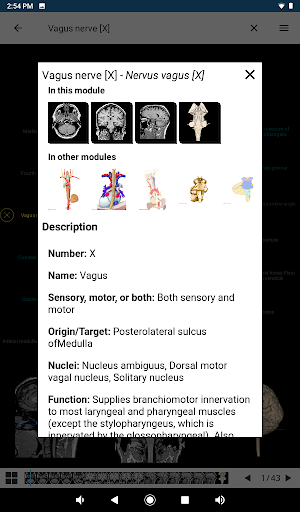

*Improved detail view of anatomical parts for easier identification in images of the current and other modules.

*Improved visibility of anatomical parts definitions

*Browse between anatomical parts using description links